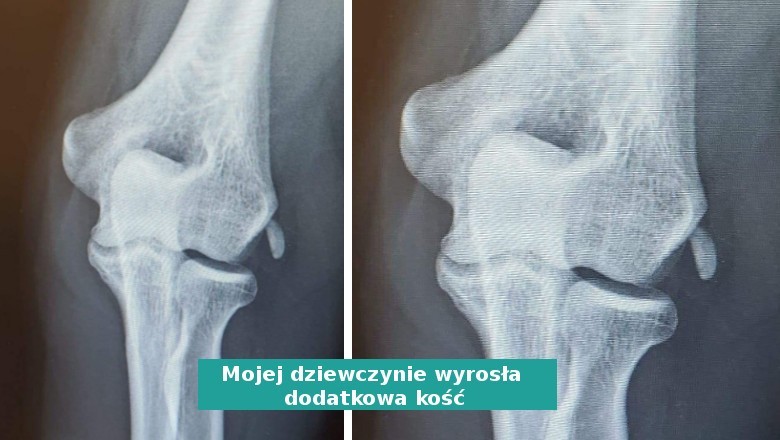

1. "Moja dziewczyna żartuje, że piła tak dużo mleka, że aż wyrosła jej dodatkowa kość."

"Moja dziewczyna żartuje, że  piła tak dużo mleka, że aż wyrosła jej dodatkowa kość." © Philobus / Reddit